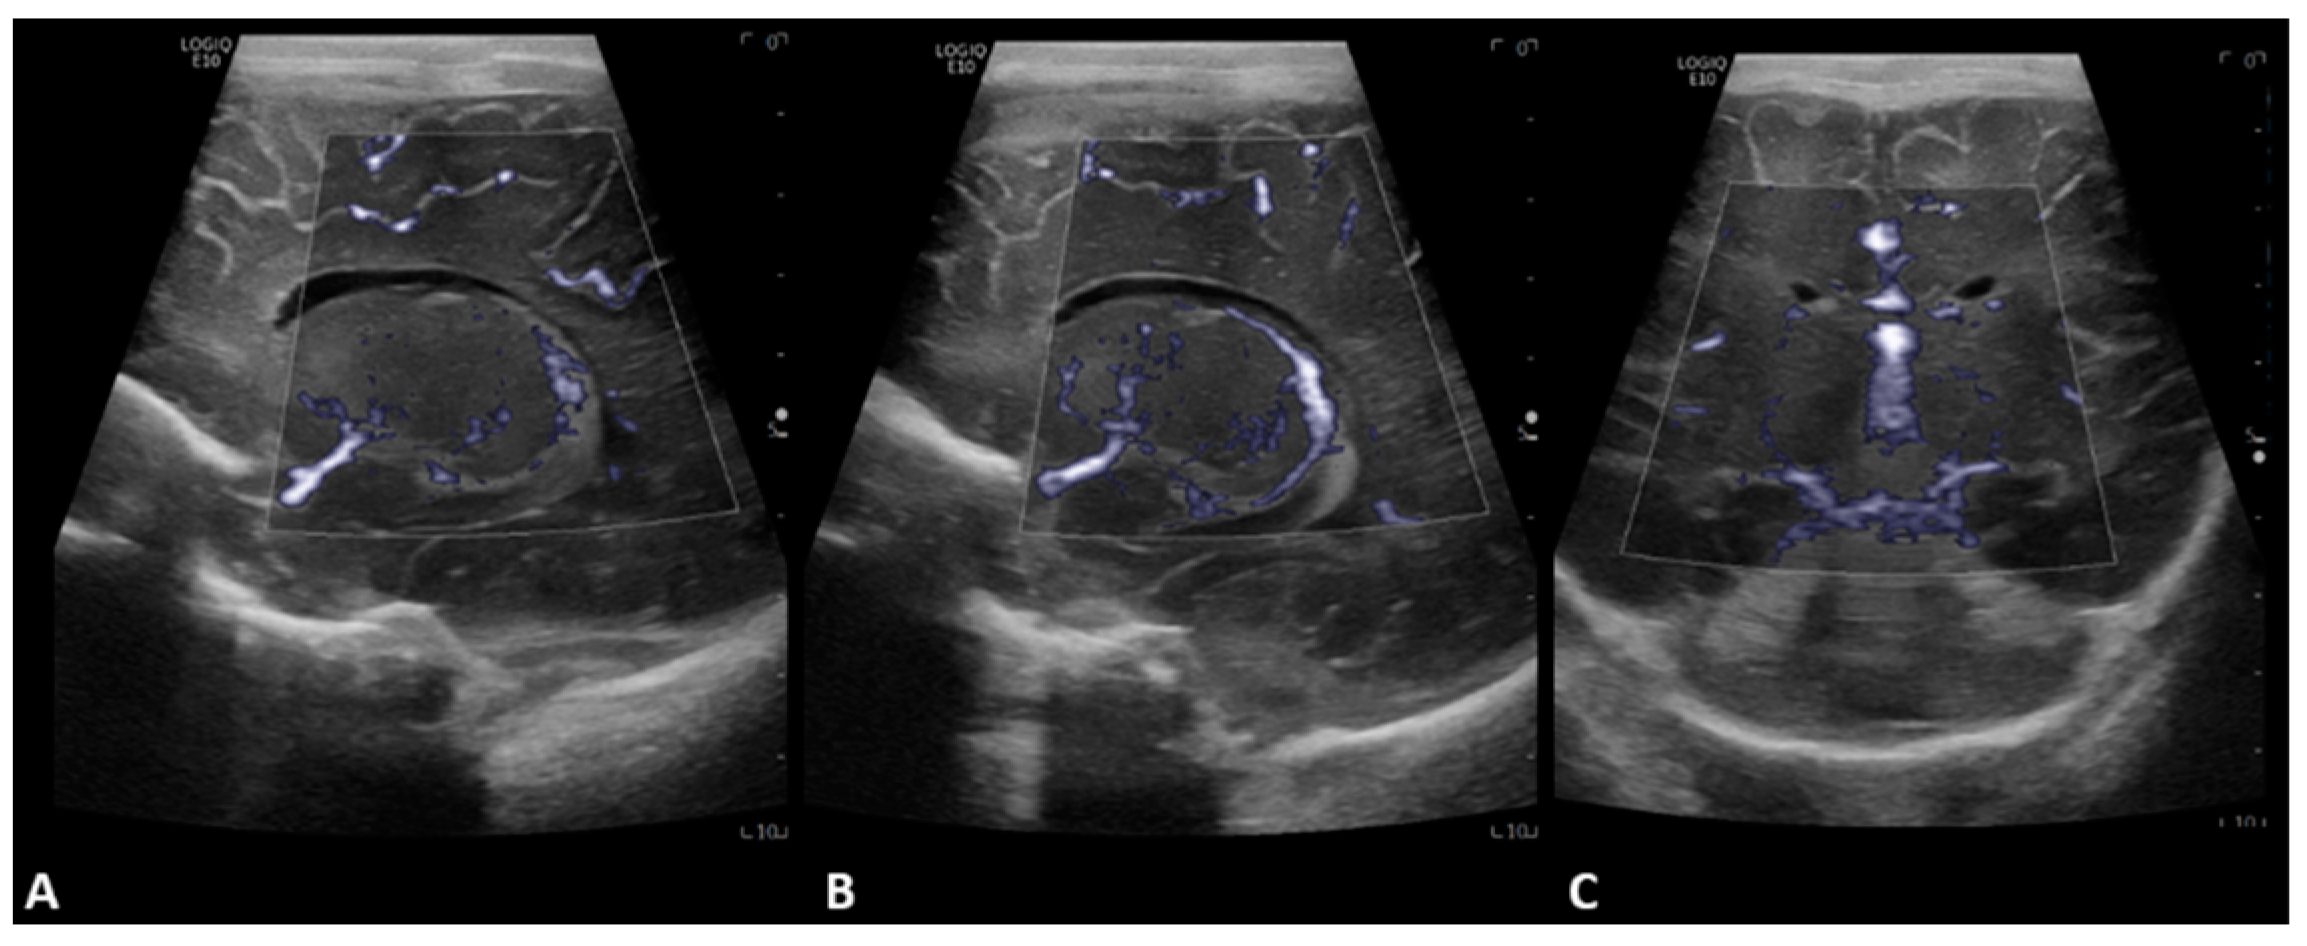

- Hwang, M.; Haddad, S.; Tierradentro-Garcia, L.O.; Alves, C.A.; Taylor, G.A.; Darge, K. Current understanding and future potential applications of cerebral microvascular imaging in infants. Br. J. Radiol. 2022, 95, 20211051. [Google Scholar] [CrossRef] [PubMed]

- Barletta, A.; Balbi, M.; Surace, A.; Caroli, A.; Radaelli, S.; Musto, F.; Saruggia, M.; Mangili, G.; Gerevini, S.; Sironi, S. Cerebral superb microvascular imaging in preterm neonates: In vivo evaluation of thalamic, striatal, and extrastriatal angioarchitecture. Neuroradiology 2021, 63, 1103–1112. [Google Scholar] [CrossRef]

- Goeral, K.; Hojreh, A.; Kasprian, G.; Klebermass-Schrehof, K.; Weber, M.; Mitter, C.; Berger, A.; Prayer, D.; Brugger, P.C.; Vergesslich-Rothschild, K.; et al. Microvessel ultrasound of neonatal brain parenchyma: Feasibility, reproducibility, and normal imaging features by superb microvascular imaging (SMI). Eur. Radiol. 2019, 29, 2127–2136. [Google Scholar] [CrossRef] [PubMed]

- Lyo, S.; Tierradentro-Garcia, L.O.; Viaene, A.N.; Hwang, M. High-resolution neurosonographic examination of the lenticulostriate vessels in neonates with hypoxic-ischemic encephalopathy. Br. J. Radiol. 2022, 95, 20211141. [Google Scholar] [CrossRef] [PubMed]